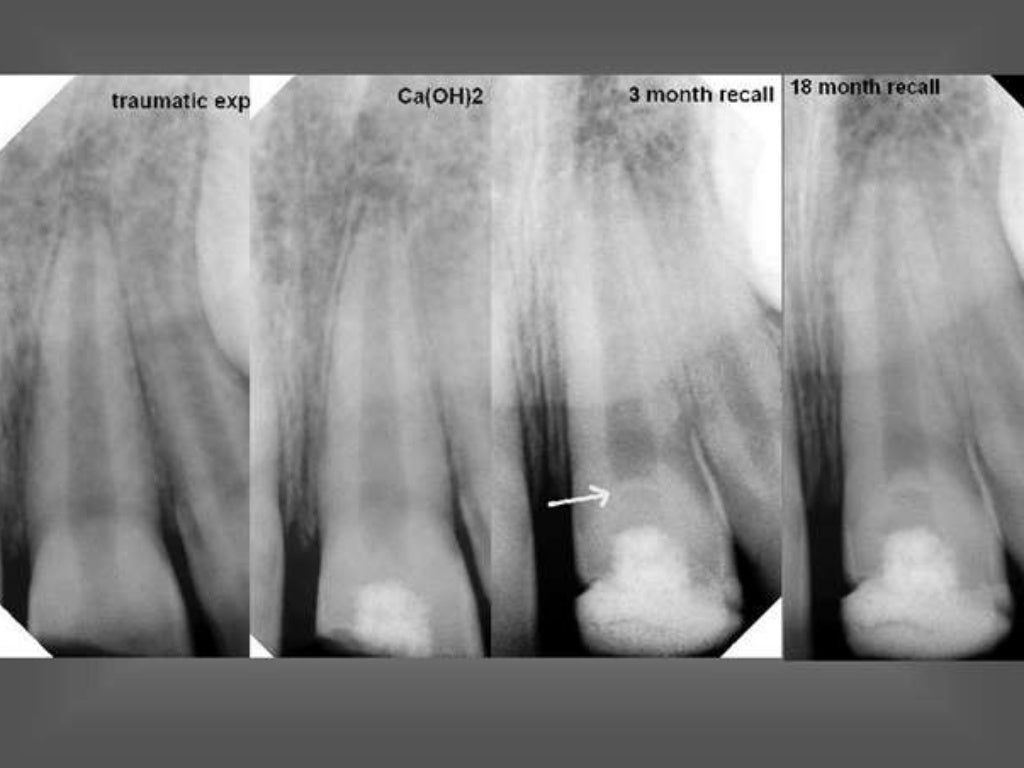

Figure 1 from Apexification in open apices with mineral trioxide What Is Apexification apexification is a method to induce a calcified barrier in a root with an open apex or the continued apical development of an incomplete root in teeth with necrotic pulps. apexification is a procedure that helps close incomplete tooth roots before a root canal can be performed. apexification is a dental procedure to close an open tooth. What Is Apexification.